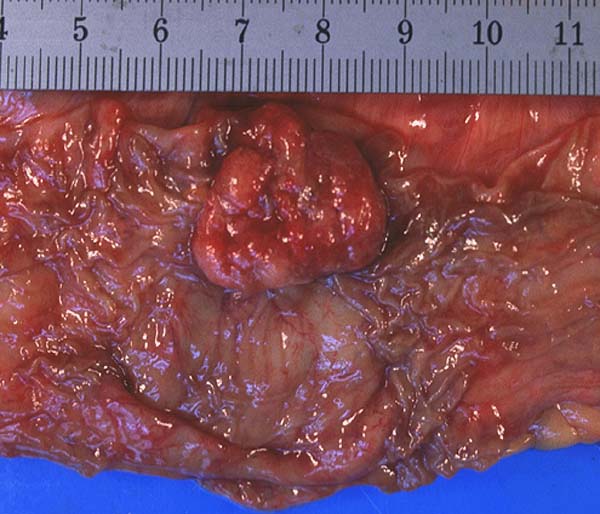

Konventionelle Kolonschleimhautadenome können makroskopisch als erhabene, flache oder eingesenkte Läsionen imponieren. Nicht alle Adenome imponieren also makroskopisch als Polypen. Die erhabenen Adenome können gestielt oder sessil sein. Für die Diagnose entscheidend ist der Nachweis einer Epitheldysplasie. Bei der Gradierung der Dysplasie (> 25) werden Polaritätsverlust, Drüsenkomplexität, Zelldichte und Ausmass der zytologischen Atypien berücksichtigt. Mikroskopisch unterscheidet man tubuläre (>80% Tubuli) (> 1113), villöse (>80% Villi) (> 503) und tubulovillöse Adenome. Am häufigsten sind tubuläre Adenome gefolgt von gemischten, rein villöse sind selten (5%). Die Unterscheidung von Villi und längs angeschnittenen Tubuli ist fliessend. Ein Villus (> 502) wird arbiträr definiert als Drüse, deren Länge mindestens das Doppelte der normalen Mukosadicke beträgt.

• Ein polypoides Kolonschleimhautfragment.

• Das Adenom besteht teilweise aus langen fingerförmigen verzweigten villösen Strukturen und kürzeren unverzweigten Tubuli.